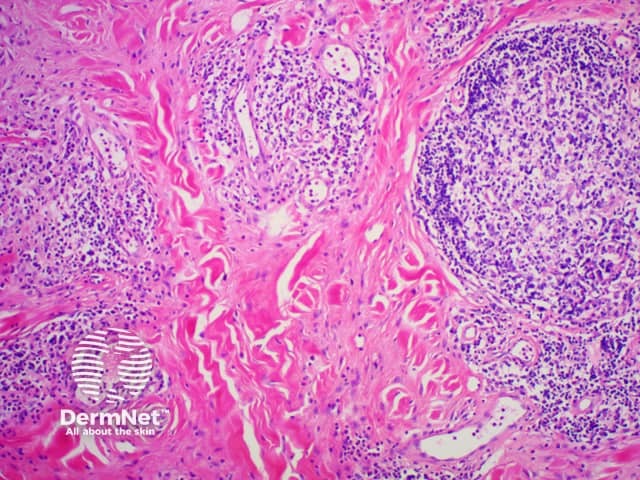

Figure 2

Yokura et al (2014) proposed a classification of IgG4-related skin disease which divides it into primary, mass-forming lesions due to the direct infiltration of plasma cells and secondary lesions which are due to IgG4-mediated inflammation through secondary mechanisms.

The diagnostic criteria on histology proposed for skin disease are the following: